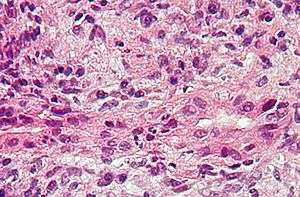

- Hepatitis, inflammation of the liver, is caused by various viruses (viral hepatitis) also by some liver toxins (e.g. alcoholic hepatitis), autoimmunity (autoimmune hepatitis) or hereditary conditions.[4]

- Cirrhosis is the formation of fibrous tissue (fibrosis) in the place of liver cells that have died due to a variety of causes, including viral hepatitis, alcohol overconsumption, and other forms of liver toxicity. Cirrhosis causes chronic liver failure.[13]

Liver disease can occur through several mechanisms. A common form of liver disease is viral infection. Viral hepatitides such as Hepatitis B virus and Hepatitis C virus can be vertically transmitted during birth via contact with infected blood.[18][19] According to a 2012 NICE publication, "about 85% of hepatitis B infections in newborns become chronic".[20] In occult cases, Hepatitis B virus is present by HBV DNA, but testing for HBsAg is negative.[21] High consumption of alcohol can lead to several forms of liver disease including alcoholic hepatitis, alcoholic fatty liver disease, cirrhosis, and liver cancer.[22] In the earlier stages of alcoholic liver disease, fat builds up in the liver's cells due to increased creation of triglycerides and fatty acids and a decreased ability to break down fatty acids.[23] Progression of the disease can lead to liver inflammation from the excess fat in the liver. Scarring in the liver often occurs as the body attempts to heal and extensive scarring can lead to the development of cirrhosis in more advanced stages of the disease.[23] Approximately 3-10% of individuals with cirrhosis develop a form of liver cancer known as hepatocellular carcinoma.[23]